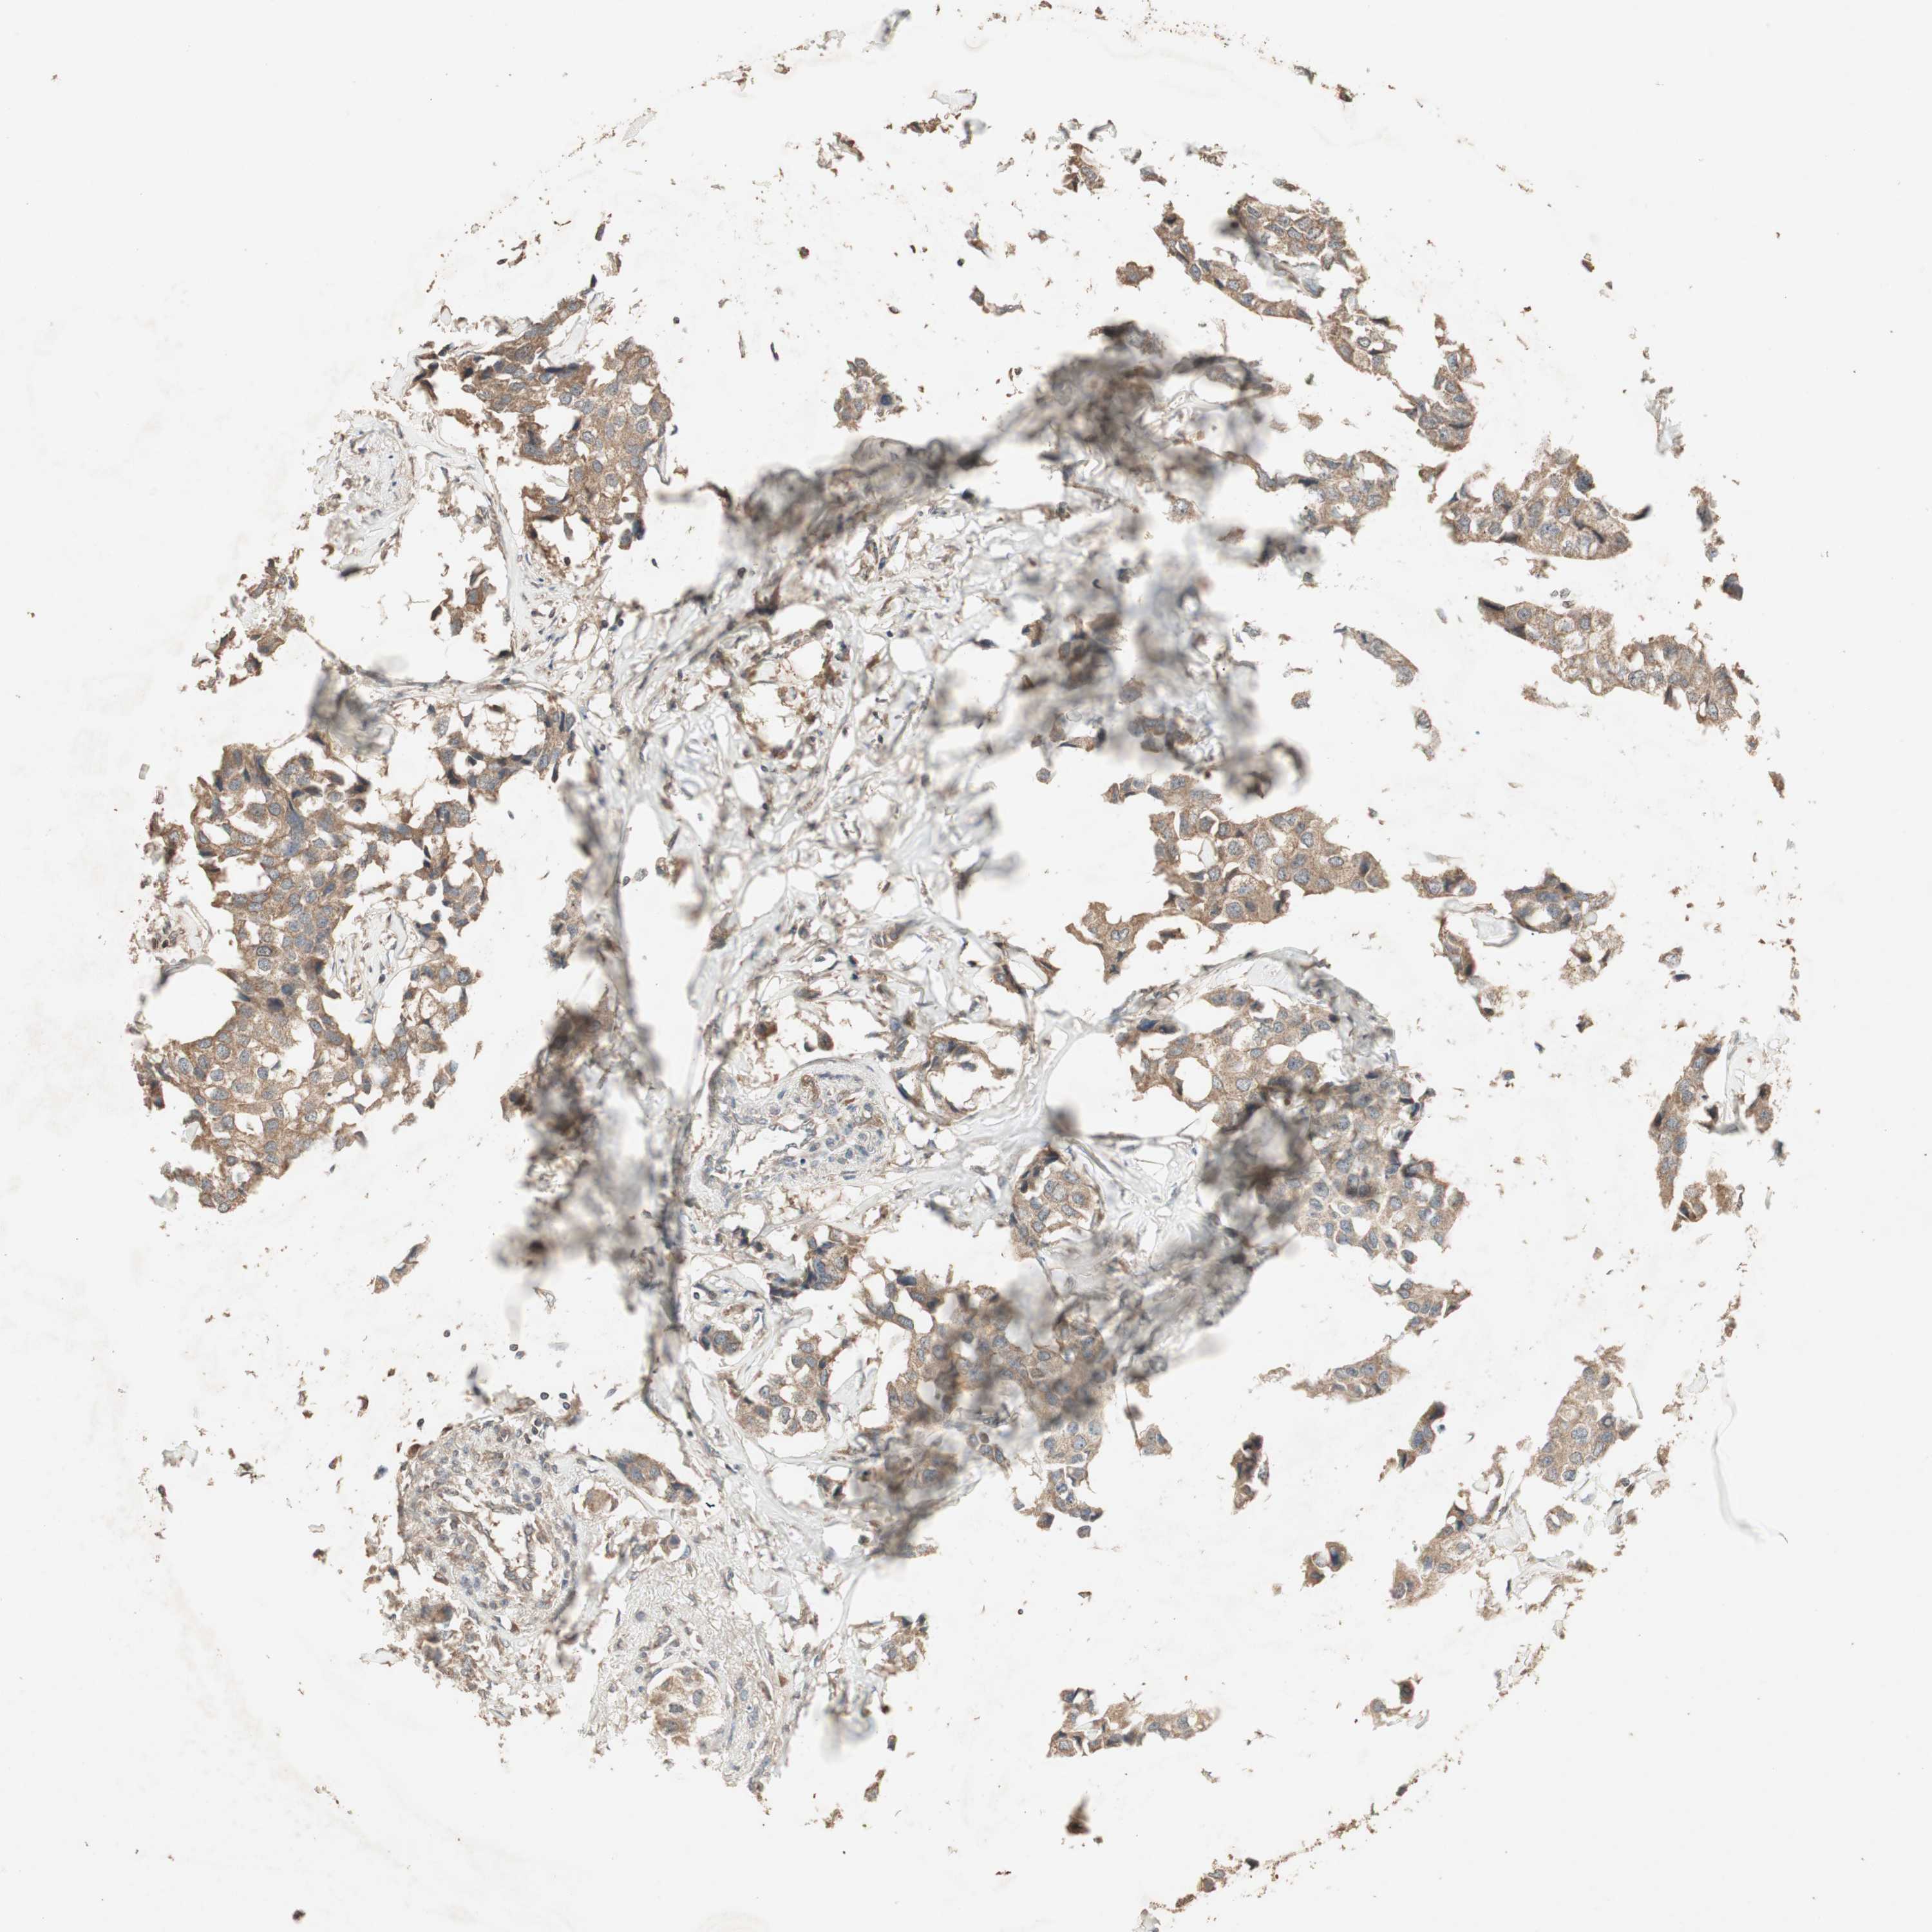

BRCA TCGA BRCA VALIDATION PROTEIN EXPRESSION